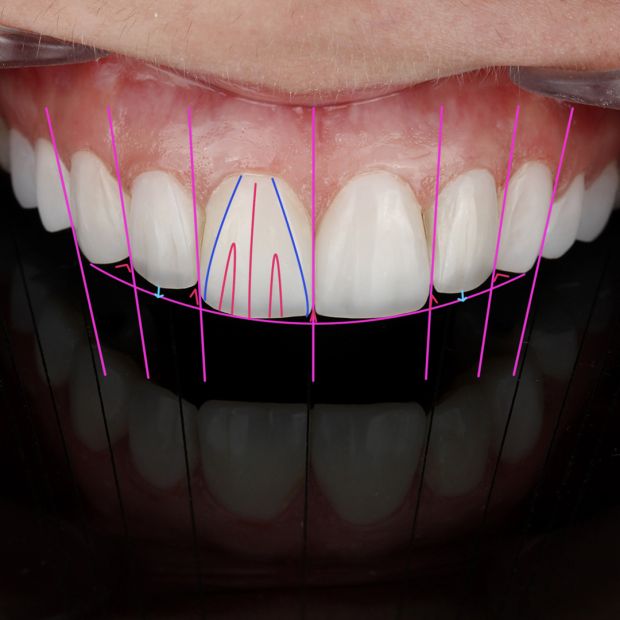

smile design

If you are skeptical about the outcome of your smile makeour results, Or you are wondering about the type of the treatment suitable for you, digital smile design will do wonders for you.

In this technique using dental photography and digital software, your smile is analyzed and digilally designed to perfection, presenting you with the probable outcome of the suggested treatment designed specifically for you.